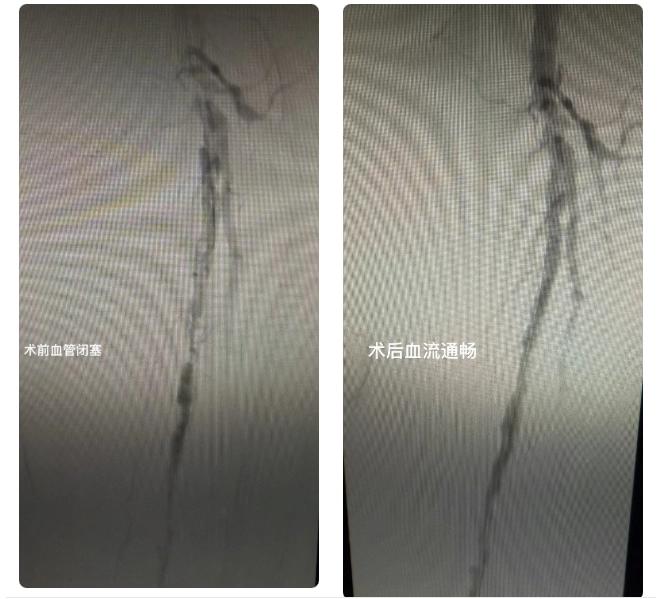

上图为左侧下肢动脉闭塞导致肢体缺血坏死患者,若不及时治疗,坏死范围将持续扩大,最终可能面临截肢。肝胆心胸外科为其实施“左下肢动脉球囊扩张+支架植入术”。术后原本发黑坏死的足部组织逐渐转好,之前疼得睡不着觉,现在能正常走路了!家属看着老人日渐康复的状态,对肝胆心胸外科的医术和责任心赞不绝口纷纷竖起大拇指。